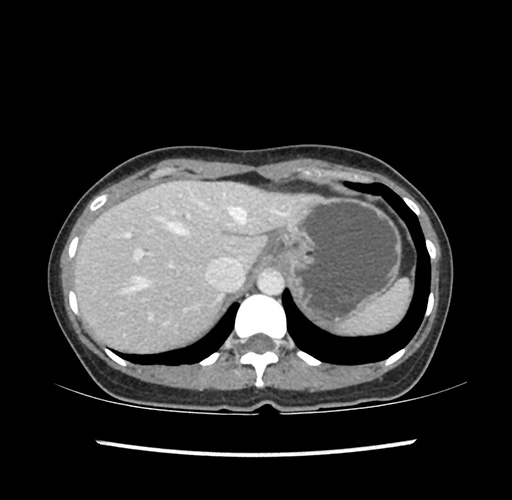

Imaging Analysis

Look through the patient's CT scan to identify any areas of concern for the necessary procedure.

Based on your CT findings, which issue(s) would give reason for "planned slowing down moment(s)" in this case?

Considering a standard left lateral sectionectomy procedure, what step(s) of the operation would you do differently in this case ?